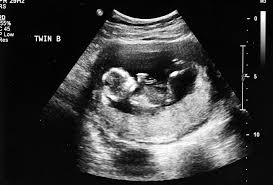

يمكن، باستخدام الموجات فوق الصوتية، لطبيب التوليد قياس معدل ضربات قلب الجنين في وقت مبكر من ستة إلى ثمانية أسابيع من الحمل. ويتراوح متوسط معدل ضربات قلب الجنين من 110 إلى 160 نبضة في الدقيقة ويتغير عندما يكون الطفل نشطًا.

عادةً ما يجري تحديد جنس الطفل خلال الموجات فوق الصوتية وذلك في الثلث الثاني من الحمل. ويتم إجراؤه في الأسبوع العشرين تقريبًا من الحمل ويتحقق أيضا من نمو الطفل وسلامته.

تقول الدكتور لابين: “خلال هذا الموجات فوق الصوتية، عادة ما نكون قادرين على تحديد الأعضاء التناسلية للذكور والإناث”. مضيفة: “ولكن قبل 16 أسبوعًا أو نحو ذلك، لا تعد الموجات فوق الصوتية طريقة موثوقة لتحديد جنس الجنين”.